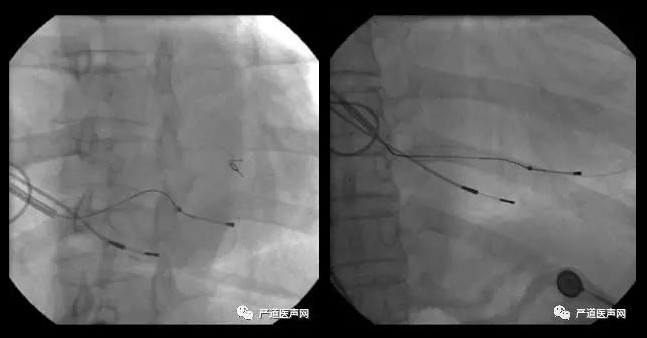

手术过程:尝试多个部位放置电极,起搏阈值均过高。

起搏阈值5V 起搏阈值6V

双导丝寻找其他血管 双导丝加强支撑

起搏阈值1V